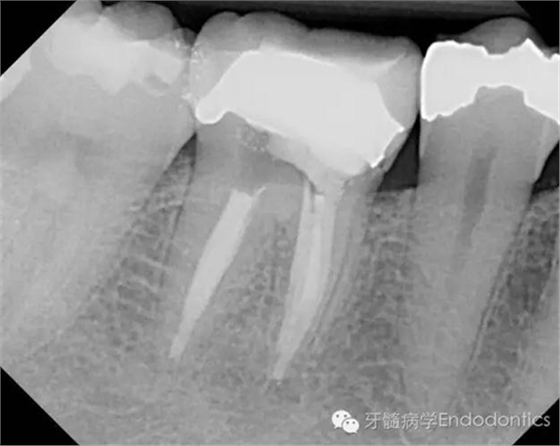

兩年后復診,病變愈合。

圖6.隨訪兩年后X線片